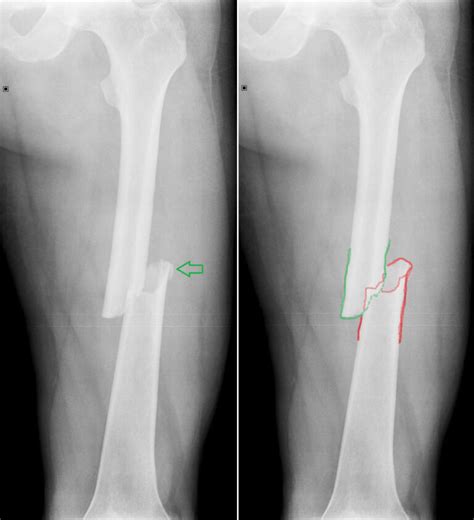

Zlomenina zubu

Čím je pes starší, tým sú jeho zuby krehkejšie. Psy, ktoré boli v mladosti nevhodne kŕmené, môžu mať sklony k lámavosti zubov rovnako ako tie, ktoré si ich poškodili v dôsledku zlozvyku (hryzenie pletiva či zbieranie kameňov). Pokiaľ si majiteľ zlomený zub včas všimne, dá sa jeho odstránením zachrániť zvyšok ústnej dutiny. Neošetrený zub je totiž zdrojom rôznych infekcií. Pes, ktorý trpí lámavosťou zubov, by mal chodiť na prechádzky s náhubkom, aby sa vyhol pokušeniu hrýzť pevné predmety.

Zlomeniny zubov sa vyskytujú rovnako ako u psov tak aj u mačiek. Zlomeniny sa rozdeľujú na nekomplikované a komplikované. Prvé spomenuté nezasahujú do zubnej drene. Komplikované fraktúry zubnú dreň otvárajú, a tým umožňujú prienik baktérií do drene zuba. Pokiaľ je zlomenina nekomplikovaná, väčšinou nie je potrebné žiadne ošetrenie. Pri komplikovaných zlomeninách je nutné ošetrenie, ktoré môže zahŕňať vitálnu amputáciu pulpy alebo endodontickú výplň. Prvý spôsob je možné vykonať do 48 hodín po úraze u psov straších ako 18 mesiacov. U psov mladších ako 18 mesiacov je možné daný zákrok vykonať až do 14 dní po úraze. Každým dňom navyše sa však šanca na úspech znižuje. Vitálnou amputáciou drene je možné zachovať zub vitálny (živý). Ak došlo k úrazu dávnejšie, prípadne zubná dreň odumrela, je potrebné ju odstrániť a kanál endodonticky ošetriť. Pri tomto zákroku sa kanál pomocou špeciálnych nástrojov vyčistí a potom vyplní gutaperčou, ktorá v kanáli stvrdne a zabezpečí tak tvrdosť a odolnosť zubu.

Aj mléčný zub se může zlomit a bolí stejně, jako zlomený zub trvalý. Vyhledejte veterináře stomatologa a nechte zvíře ošetřit. Zlomený mléčný zub je vhodné vytrhnout co nejdříve, ještě než se u jeho kořene vyvine zánět. Ten může poškodit vývoj trvalého zubu, který je schovaný pod ním.

Zlomený trvalý zub u mladého zvířete (do 18 měsíců věku): Vyhledejte veterináře stomatologa co nejdříve. Zlomený zub se musí ošetřit včas, než dojde k úplnému odumření zubní dřeně. Nejvhodnější je nechat zub ošetřit co nejdříve, aby se zvýšila šance na zachování vitality zubu. Po 10-14 dnech je zubní dřeň nenávratně ztracena, zub odumře a bude zeslabený. Ošetření je pak komplikovanější, pacienta čeká více ošetření v anestezii nebo dokonce ztráta celého zubu.

Zlomený zub u dospělého psa (nad 18 měsíců věku): Opět platí, že zub by měl být ošetřen co nejdříve. U staršího psa je už dokončen vývoj kořene, ale regenerační schopnost zubní dřeně klesá. Proto musí být čerstvá zlomenina zubu ošetřena do dvou dnů. Pokud dojde k prodlevě, je zubní dřeň nenávratně ztracena a zub odumře. Pacienta v takovém případě čeká endodontické ošetření (vyčištění a zaplnění kořenového kanálku), které je časově i finančně náročnější.